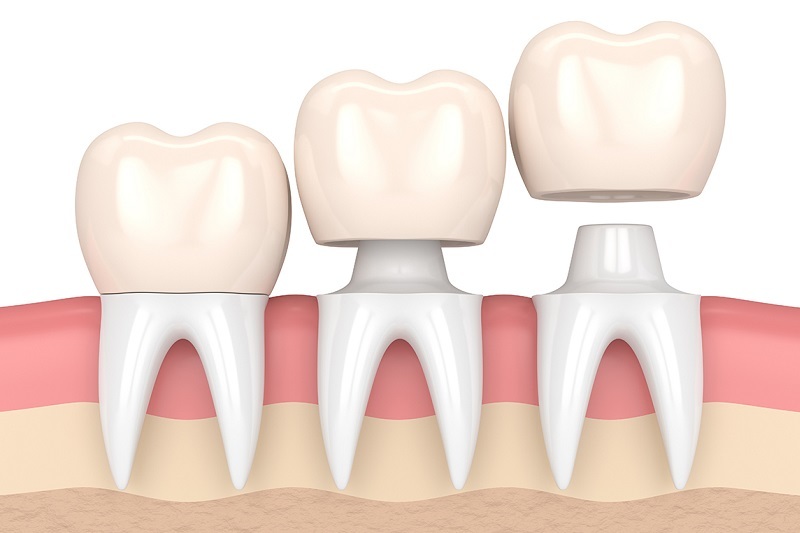

Bọc lại răng sứ là điều bạn sẽ phải thực hiện nếu sau một thời gian sử dụng, vì một lý do nào đó răng của bạn không thể nào đáp ứng được nhu cầu về thẩm mỹ cũng như chức năng. Vậy răng sứ có độ bền bao lâu và khi nào nên bọc lại răng sứ? Hãy cùng nha khoa hiDental tìm lời giải đáp nhé!

Răng sứ có độ bền khá cao, tuổi thọ của một chiếc răng sứ có thể lên đến hơn 10 năm tùy vào loại vật liệu được sử dụng cũng như cách chăm sóc răng miệng. Ngoài ra, yếu tố chất lượng phòng nha và tay nghề của bác sĩ cũng góp phần ảnh hưởng đến độ bền của răng sứ.

Khi nào nên bọc lại răng sứ

Bạn nên thực hiện bọc lại răng sứ khi có những dấu hiệu sau đây:

- Răng sau một thời gian bị đen viền nướu

- Có dấu hiệu bị viêm nướu

- Răng sứ bị nứt mẻ, gãy vỡ

- Không đáp ứng được nhu cầu về thẩm mỹ cũng như chức năng

Nếu xuất hiện các tình trạng ấy, bạn nên đến ngay các nha khoa uy tín, chất lượng để bọc lại răng sứ. Giúp cho hàm răng của bạn đảm bảo tính thẩm mỹ, an toàn, thoải mái khi sử dụng và không gây hại cho sức khỏe.